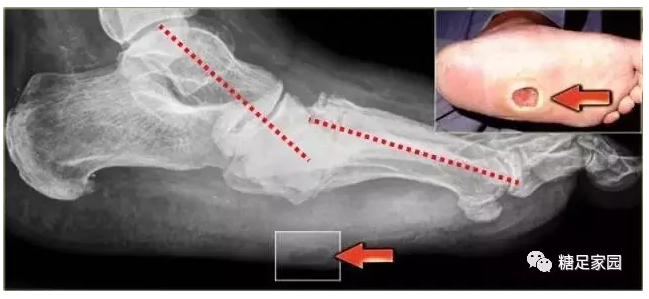

糖尿病足的护理--夏科氏足(3)_xiaomeng

糖尿病足-认识夏科氏足病 - 好大夫在线